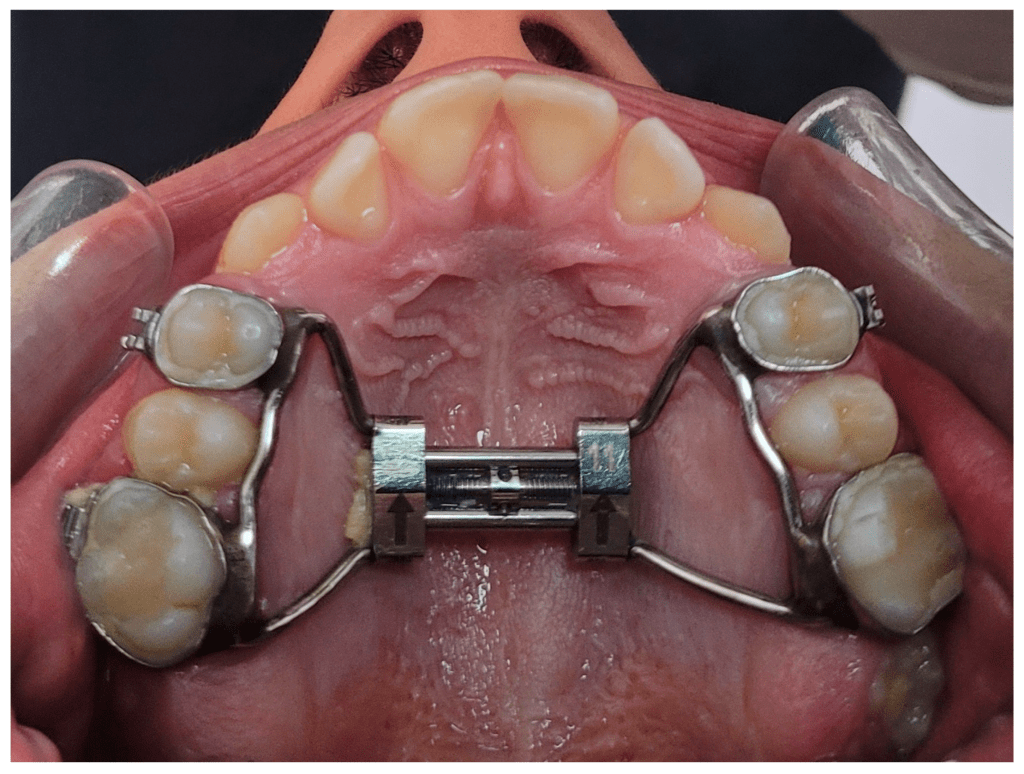

- Expansão rápida assistida por mini-implantes (MARPE), que direciona as forças de expansão ao osso basal;

- Expansão rápida da maxila cirurgicamente assistida, indicada quando a resistência sutural inviabiliza a expansão ortopédica isolada.

A escolha da técnica deve considerar fatores como idade cronológica, maturação esquelética, espessura óssea palatina, padrão facial e objetivos do tratamento.

Os dispositivos mais utilizados incluem expansores do tipo Hyrax, Haas e suas variações contemporâneas, além de aparelhos assistidos por mini-implantes.